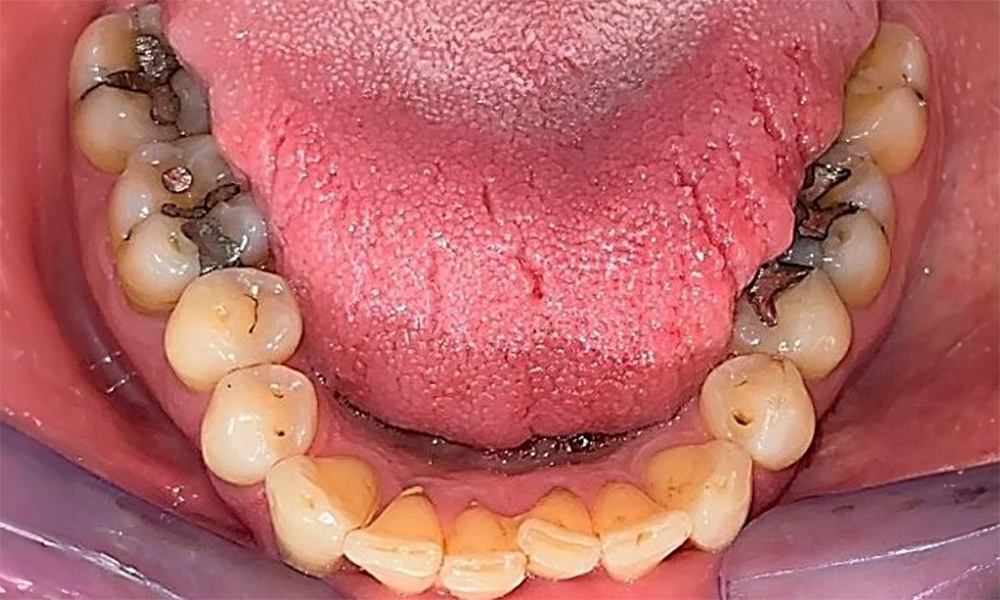

The patient has a full dentition with 28 teeth, which includes amalgam and composite fillings in the molar and premolar regions. There is a visible clinical marginal gap present on tooth 14. Tooth 27 has an adequate gold inlay. There are also generalized attritions and abrasions. (Fig. 2, Fig. 3, Fig. 4, Fig. 5, Fig. 6)

The patient has stage II, grade B periodontitis (5). At 1 to 3 mm, the clinical probing depths were within the physiological range. Localized probing depths of 5 mm were observed on the mesiopalatal aspects on both 17 and 27. There are generalized recessions of 1–3 mm with partial loss of the interdental papillae (Fig. 2, Fig. 3, Fig. 4)

The patient uses interdental brushes and an electric toothbrush. This demonstrates good compliance and good intraoral hygiene behaviour and understanding at home. Regular motivation and re-instruction are indispensable due to the risk of progression, particularly with regard to the cleaning of interdental areas, since increased probing depths were detected in these areas. Localized calculus and soft plaque was present in the lingual anterior mandibular region, and these must be shown to the patient. The interdental brush size may need to be checked and adjusted. A soft brush attachment is recommended based on the presence of exposed root surfaces to prevent wedge-shaped defects. Toothpaste with a low abrasive value should be used.